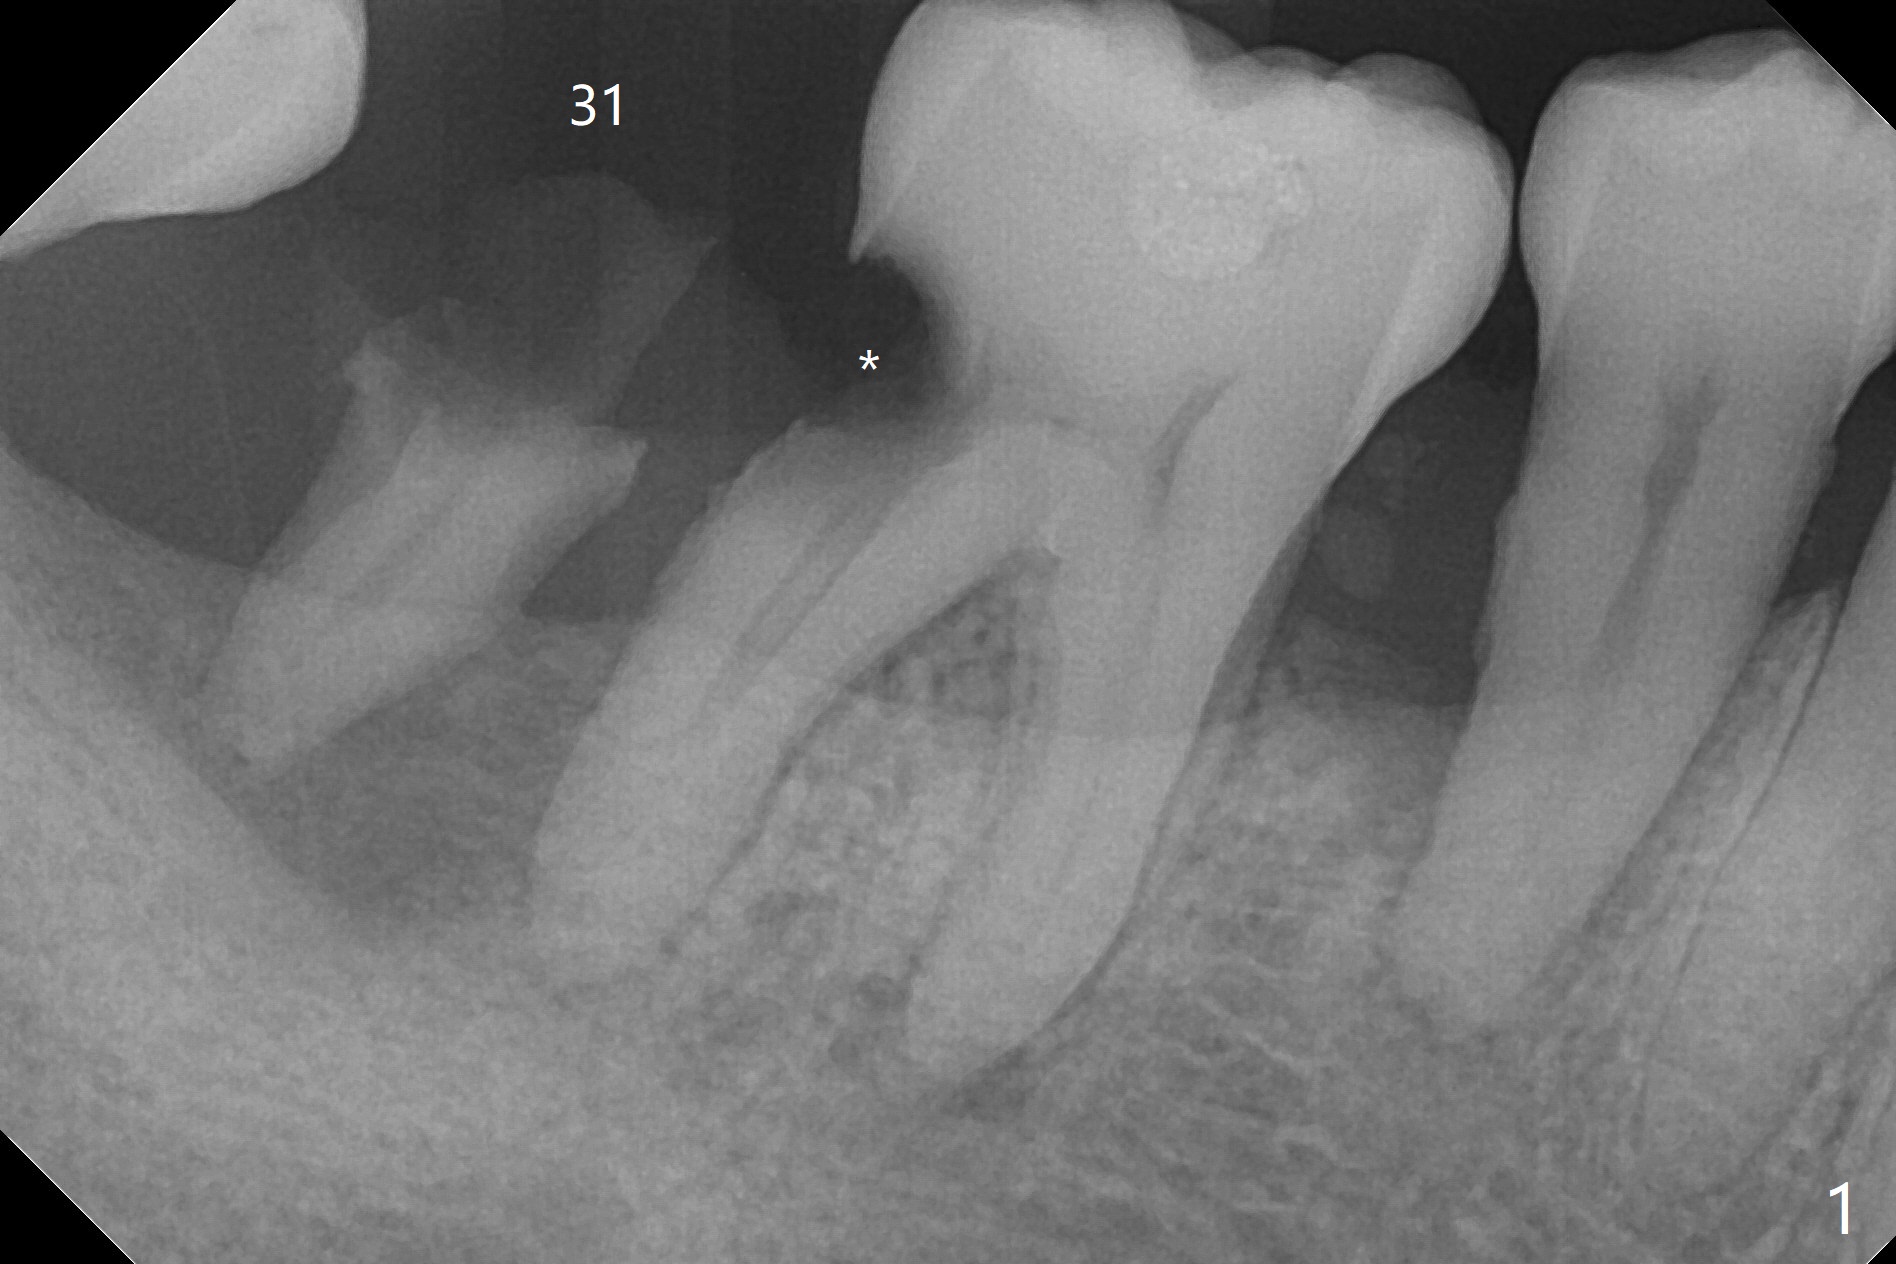

A 55-year-old woman has not visited dentists for the last 8 years. She requested extraction of the residual root of #31, although she is sensitive to cold in the area (caries in DO of #30, Fig.1: *). Bone graft was not prepared until the root was taken out. The socket was too big to heal by itself for implant. Bleeding is controlled by insertion of gauze with 1:100,000 Epinephrine. With consent, cortical bone was placed after mixing with blood (Fig.2) and covered with 8x8 mm BioXclude. Acrylic dressing is applied with intention to engagement into the DO of #30 for retention (Fig.2 >). Return to Protect Graft 尖牙即种 Xin Wei, DDS, PhD, MS 1st edition 05/24/2021, last revision 05/31/2021